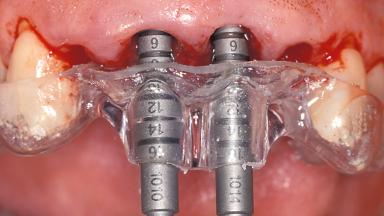

Replacement of the Four Maxillary Incisors with a Fixed Dental Prosthesis Using an Immediate Loading Protocol

In November 2001, a 53-year-old female presented seeking advice and options for treatment of her maxillary incisor teeth. She was dissatisfied with both the functional and esthetic qualities of her existing restorations. Her medical health was excellent, and she reported no contraindications to dental care. On presentation, the patient’s dental health was less than ideal. Although she had no probing depths greater than 3 mm, she suffered from generalized chronic adult periodontitis and displayed multiple sites of bleeding on probing. Her remaining dentition was heavily restored, and many teeth had been endodontically treated. Areas of recurrent dental caries were noted on many teeth. Radiographically and clinically, the maxillary incisor teeth exhibited large areas of active caries, and after the splinted crowns had been removed, the teeth were determined to be non-restorable.

# of Implants 2

Type of Implants One-Piece

Placement Protocol Immediate implant placement

Tooth Site Maxillary incisor or canine

Loading Protocol Immediate